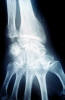

ACT Alteraciones degenerativas en muñeca.

Fractura de radio.